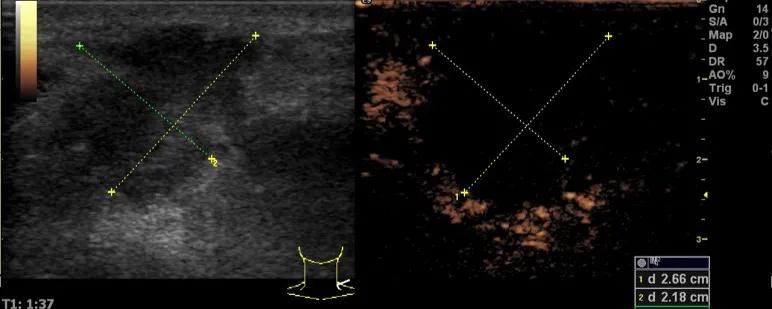

第三例是甲状腺癌患者,双侧甲状腺癌切除术后、碘治疗后一年余效果欠佳,超声显示左颈3区3枚低回声结节,穿刺示甲状腺乳头状癌转移。患者不愿意手术,希望采取局部治疗。对病灶进行液体隔离后采取热消融术,由于淋巴结较小,热消融一分钟左右完全灭活,术后增强影像显示没有脏器充填。

(病例3图例)